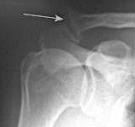

Im Röntgenbild finden sich degenerative Veränderungen wie Knochenanbauten und Verschmälerung des Gelenkspaltes. Bei alten Bandverletzungen fällt ein Höhertreten des Schlüsselbeines im Verhältnis zum Schulterdach auf. Im MRT und im Ultraschall finden sich Reizzeichen wie Flüssigkeitsansammlungen und Verdickung der Weichteile. Eine alte Bandverletzung kann durch narbige Veränderungen und Fehlstellungen im Bereich des AC-Gelenkes festgestellt werden.